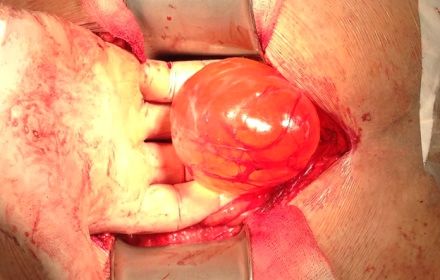

Через 3 тижні відзначено повторне збільшення рідинного освіти до колишніх розмірів. З метою позбавлення пацієнта від даного освіти, відновлення адекватного сечовипускання пацієнту виконано відкрите оперативне посібник під спінальної анестезією - екстракція кісти малого таза. Час операції склала 25 хвилин. Увечері пацієнт з відділення реанімації переведений в палату загальної терапії. Освіта видалено повністю без пошкодження сусідніх органів. При ретельному интраоперационном дослідженні встановити органну приналежність даного освіти не вдалося. Гістологічне дослідження даного освіти - проста кіста придатка яєчка.